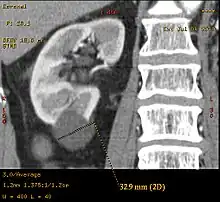

![]() | |

| Renal cyst of the left kidney (hyperintense area) as shown on MRI. | |